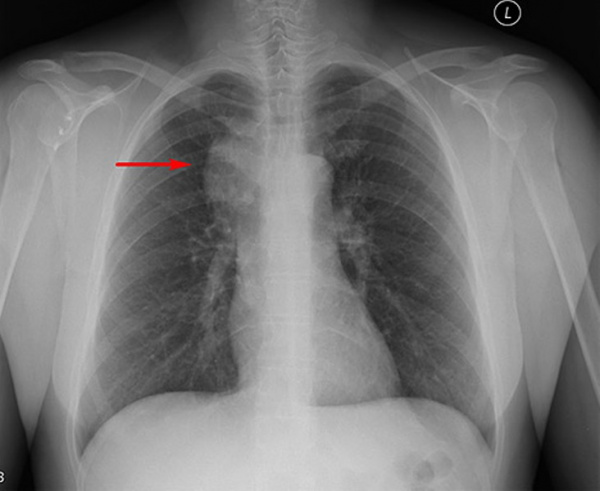

Чаще всего заболевание поражает лимфатические узлы средостения. К типичным локализациям гиперплазии также относят шейные, подмышечные и забрюшинные лимфоузлы. Лимфатический узел имеет диаметр 1-25 см, чаще всего диагностируются опухоли размером 6-7 см. Кожа над ним не изменена, субъективные неприятные ощущения отсутствуют, поэтому пациенты редко обращаются к врачу на раннем этапе.

На поздних стадиях заболевания клинические проявления зависят от локализации гиперплазированной лимфатической ткани. Поражение узлов средостения сопровождается охриплостью голоса, затруднением дыхания и глотания, болями в грудной клетке. Разрастание внутрибрюшных лимфоузлов вызывает боли в животе, диспепсические расстройства, нарушения мочеиспускания.

При локальных формах основной проблемой остается нарушение функции соседних органов. Поражение внутрибрюшных узлов чревато развитием механической кишечной непроходимости, нарушением поступления желчи в 12-перстную кишку. При поражении средостения возможна дыхательная недостаточность. При этом показатели выживаемости намного лучше: 94,5% пациентов живут дольше 5 лет после постановки диагноза.

- КТ и МРТ. Инструментальная визуализация используется для выявления лимфоидной гиперплазии, определения размеров и локализации пораженных лимфоузлов. На снимках опухолевая масса выглядит как гомогенное новообразование с четкими контурами и интенсивным накоплением контрастного вещества.